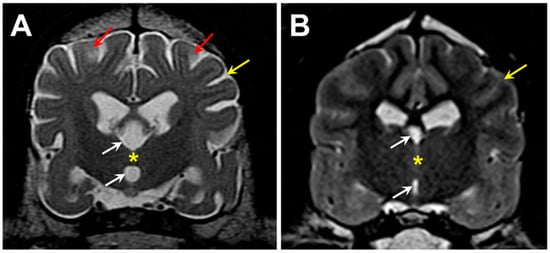

3.1. Microscopic Findings